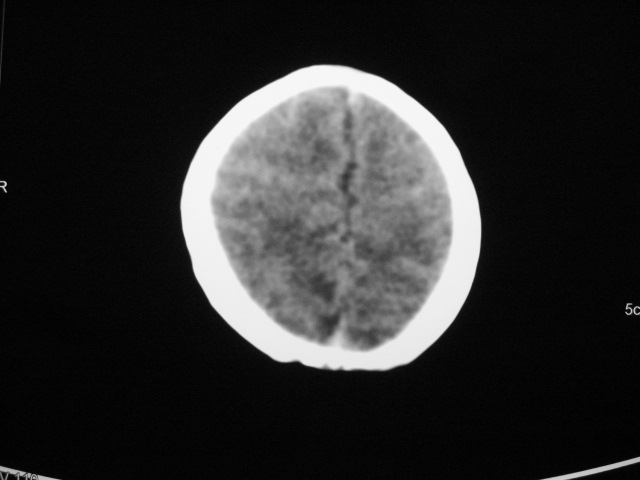

早产儿,1天,饮食呕吐,

双侧额叶见片状低密度灶,皮髓质分界模糊.患儿前囟略饱满,

支持;新生儿缺血缺氧性脑病.请密切结合临床.

患儿头颅ct示:皮质薄,髓质密度减低,脑回宽,脑沟浅,脑室系统无殊,中线结构居中,符合:早产儿颅脑ct改变。